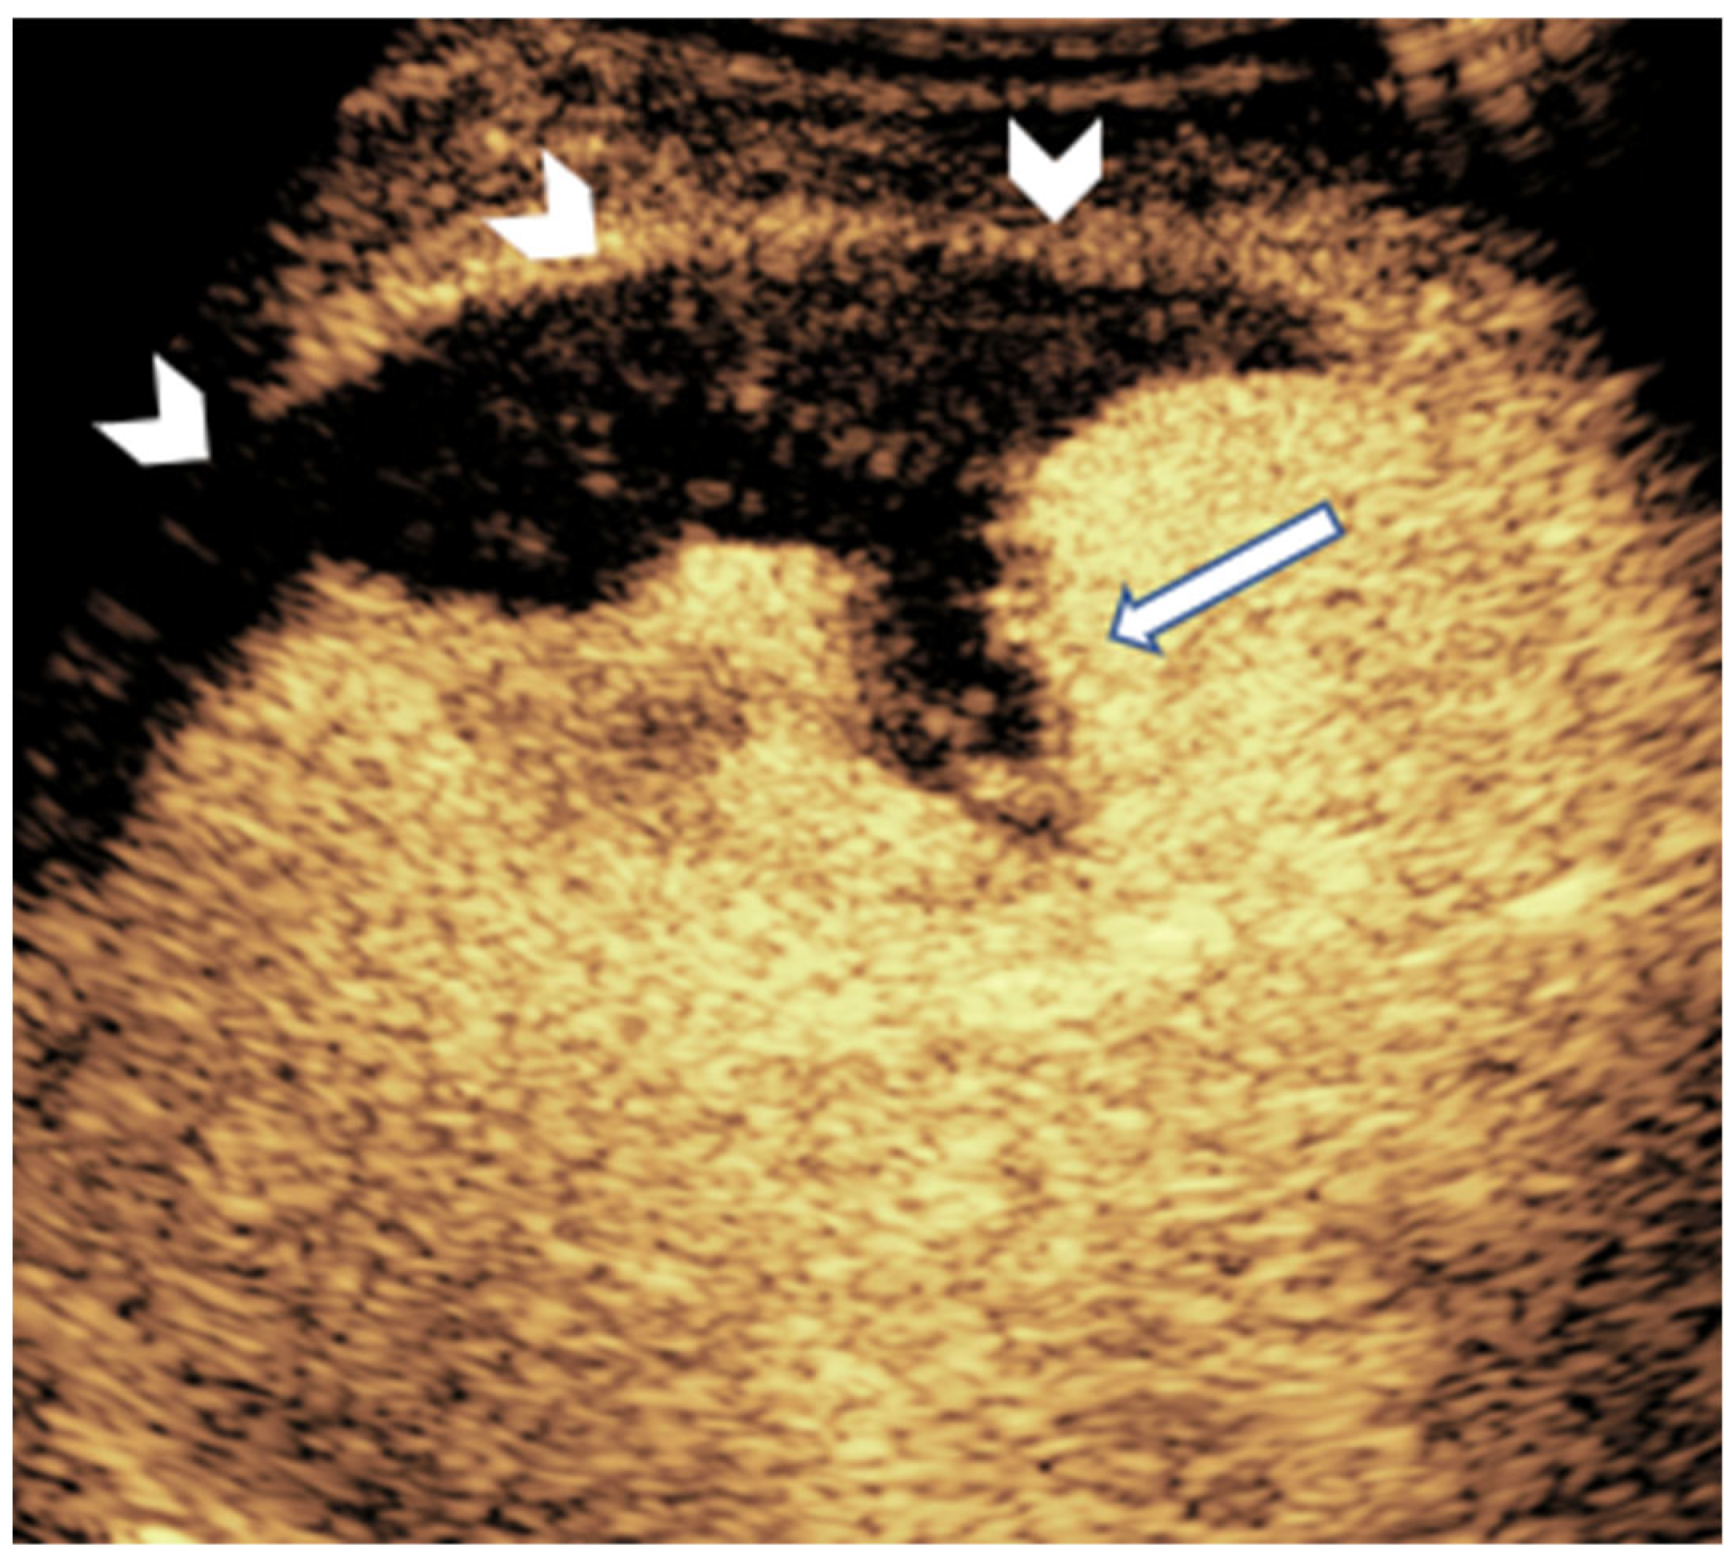

- Pšeničny, E.; Glušič, M.; Pokorn, M.; Ključevšek, D. Contrast-enhanced ultrasound in detection and follow-up of focal renal infections in children. Br. J. Radiol. 2022, 95, 20220290. [Google Scholar] [CrossRef]

- Jung, H.J.; Choi, M.H.; Pai, K.S.; Kim, H.G. Diagnostic performance of contrast-enhanced ultrasound for acute pyelonephritis in children. Sci. Rep. 2020, 10, 10715. [Google Scholar] [CrossRef]

- Rinaldo, C.; Grimaldi, D.; Di Serafino, M.; Iacobellis, F.; Verde, F.; Caruso, M.; Capasso, R.; Esposito, M.; Romeo, V.; Imbriaco, M.; et al. An update on pyelonephritis: Role of contrast-enhanced ultrasound (CEUS). J. Ultrasound 2023, 26, 333–342. [Google Scholar] [CrossRef]

- Kim, B.; Lim, H.K.; Choi, M.H.; Woo, J.Y.; Ryu, J.; Kim, S.; Park, C.M.; Lee, W.J.; Han, M.C.; Song, I.C.; et al. Detection of parenchymal abnormalities in acute pyelonephritis by pulse inversion harmonic imaging with or without microbubble ultrasonographic contrast agent: Correlation with computed tomography. J. Ultrasound Med. 2001, 20, 5–14. [Google Scholar] [CrossRef]